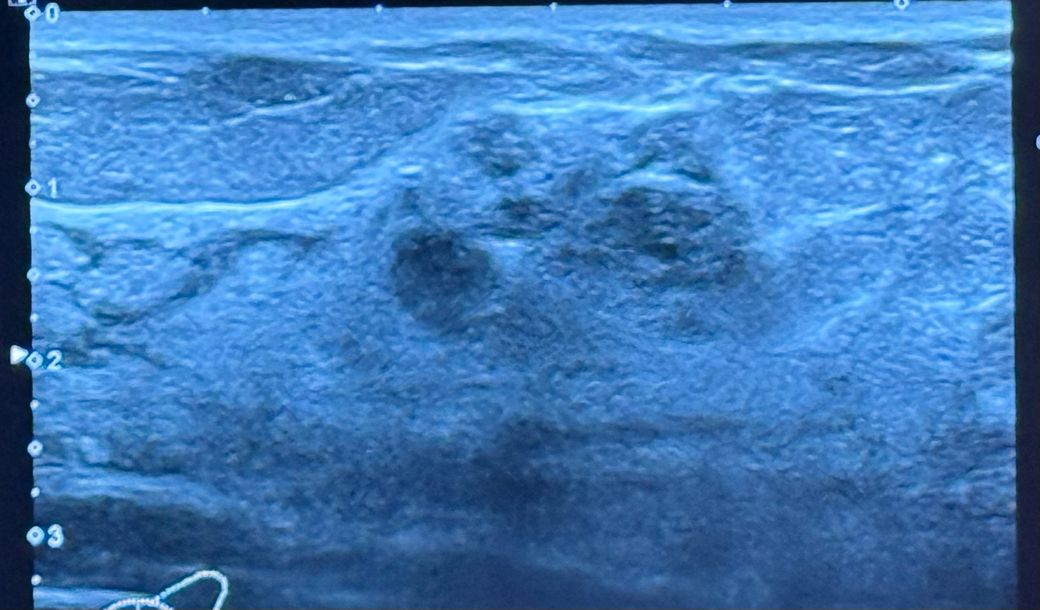

담당 선생님은 일반적인 암의 양상은 아닌데 2cm정도 되고, 지금 올린 초음파 혹 옆에 작은 혹이 하나 더 있고 유방 통증도 좀 있어서 조직검사를 하자 하셔서 했구요

혹시 초음파 사진 상으로 유방암일 확률이 있을지 도움주실 수 있을까요?

사진상 비교적 경계가 명확하고 주변 유방 조직에 비해 음영이 낮은 저음영의 병변으로 관찰되고 있어 악성 가능성이 높지는 않습니다. 하지만 크기가 1cm 이상이므로 악성 가능성을 완전히 배제하기는 어려워 조직검사를 권고하신 것으로 판단됩니다. 초음파 소견상 악성일 확률은 5% 내외이므로 너무 걱정하지 마시고 결과를 확인해 보시기 바랍니다.